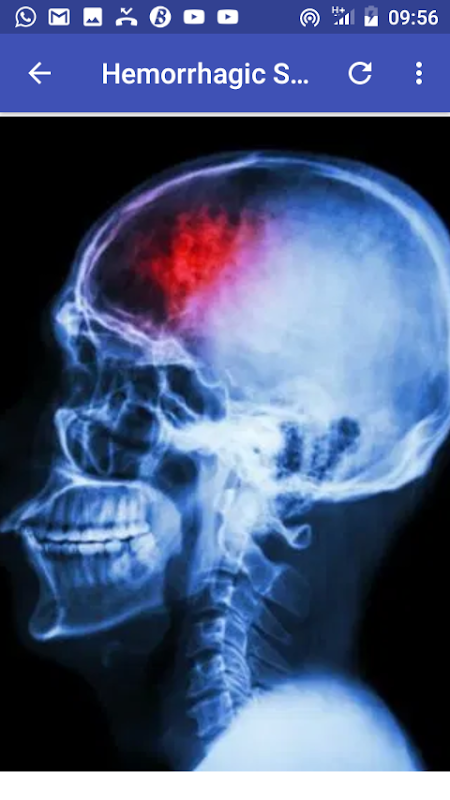

A stroke occurs when the blood supply to part of your brain is interrupted or reduced, preventing brain tissue from getting oxygen and nutrients. Brain cells begin to die in minutes.

A stroke is a medical emergency, and prompt treatment is crucial. Early action can reduce brain damage and other complications.